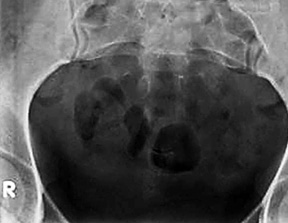

When imaging the coccyx, proper positioning and optimal exposure technique are essential to producing a diagnostic radiograph. Because the coccyx is positioned forward (kyphotic curvature) relative to the sacrum, it is not visualized anatomically with the AP sacrum. Often the pelvic brim will obstruct the coccyx unless the patient and central ray are properly aligned. When properly positioned, the PA coccyx radiograph will demonstrate the coccyx aligned with the symphysis pubis and at equal distance from the lateral wall of the pelvic inlet. (Figure 3)

Figure 3: PA view of the coccyx.

To obtain a PA coccyx, the patient stands facing the bucky as close as possible. Check feet and torso for rotation. Measure thickness at the level of the trochanters. Tube angle is 10° cephalad. Place the horizontal CR 1-2 inches above the trochanters. The vertical CR is the mid-sagittal plane. (Figure 1) Collimation is slightly less than the film size (8 x 10 portrait).